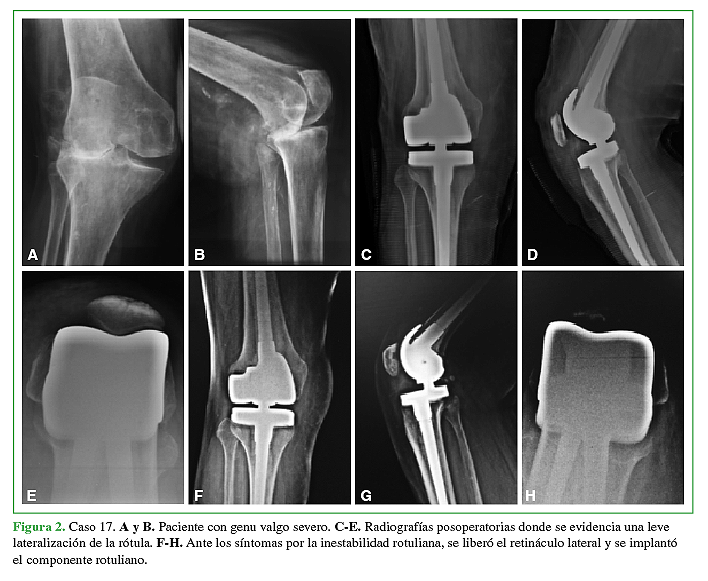

El seguimiento promedio fue de 6.5 años (rango de 2 a 12 años). El rango de movilidad conseguido fue 110º de flexión (rango de 70º – 130º) y 5º de extensión (rango de 0º a 20º). El puntaje promedio en el KSS mejoró de 38 en el preoperatorio a 82 en el postoperatorio. En la evaluación radiológica detectamos en 8 (23%) casos líneas radiolúcidas > a 2mm alrededor del componente femoral y/o tibial o alrededor de los vástagos. Cinco de 34 prótesis (14.7%) presentaron complicaciones. En 3 casos (8.9%) se trató de una infección profunda. Dos casos (5.9%) presentaron complicaciones patelo-femorales. La sobrevida de la prótesis libre de revisión a los 6.5 años fue de 94%. Si consideramos el aflojamiento aséptico como causa de revisión la sobrevida fue del 100%.